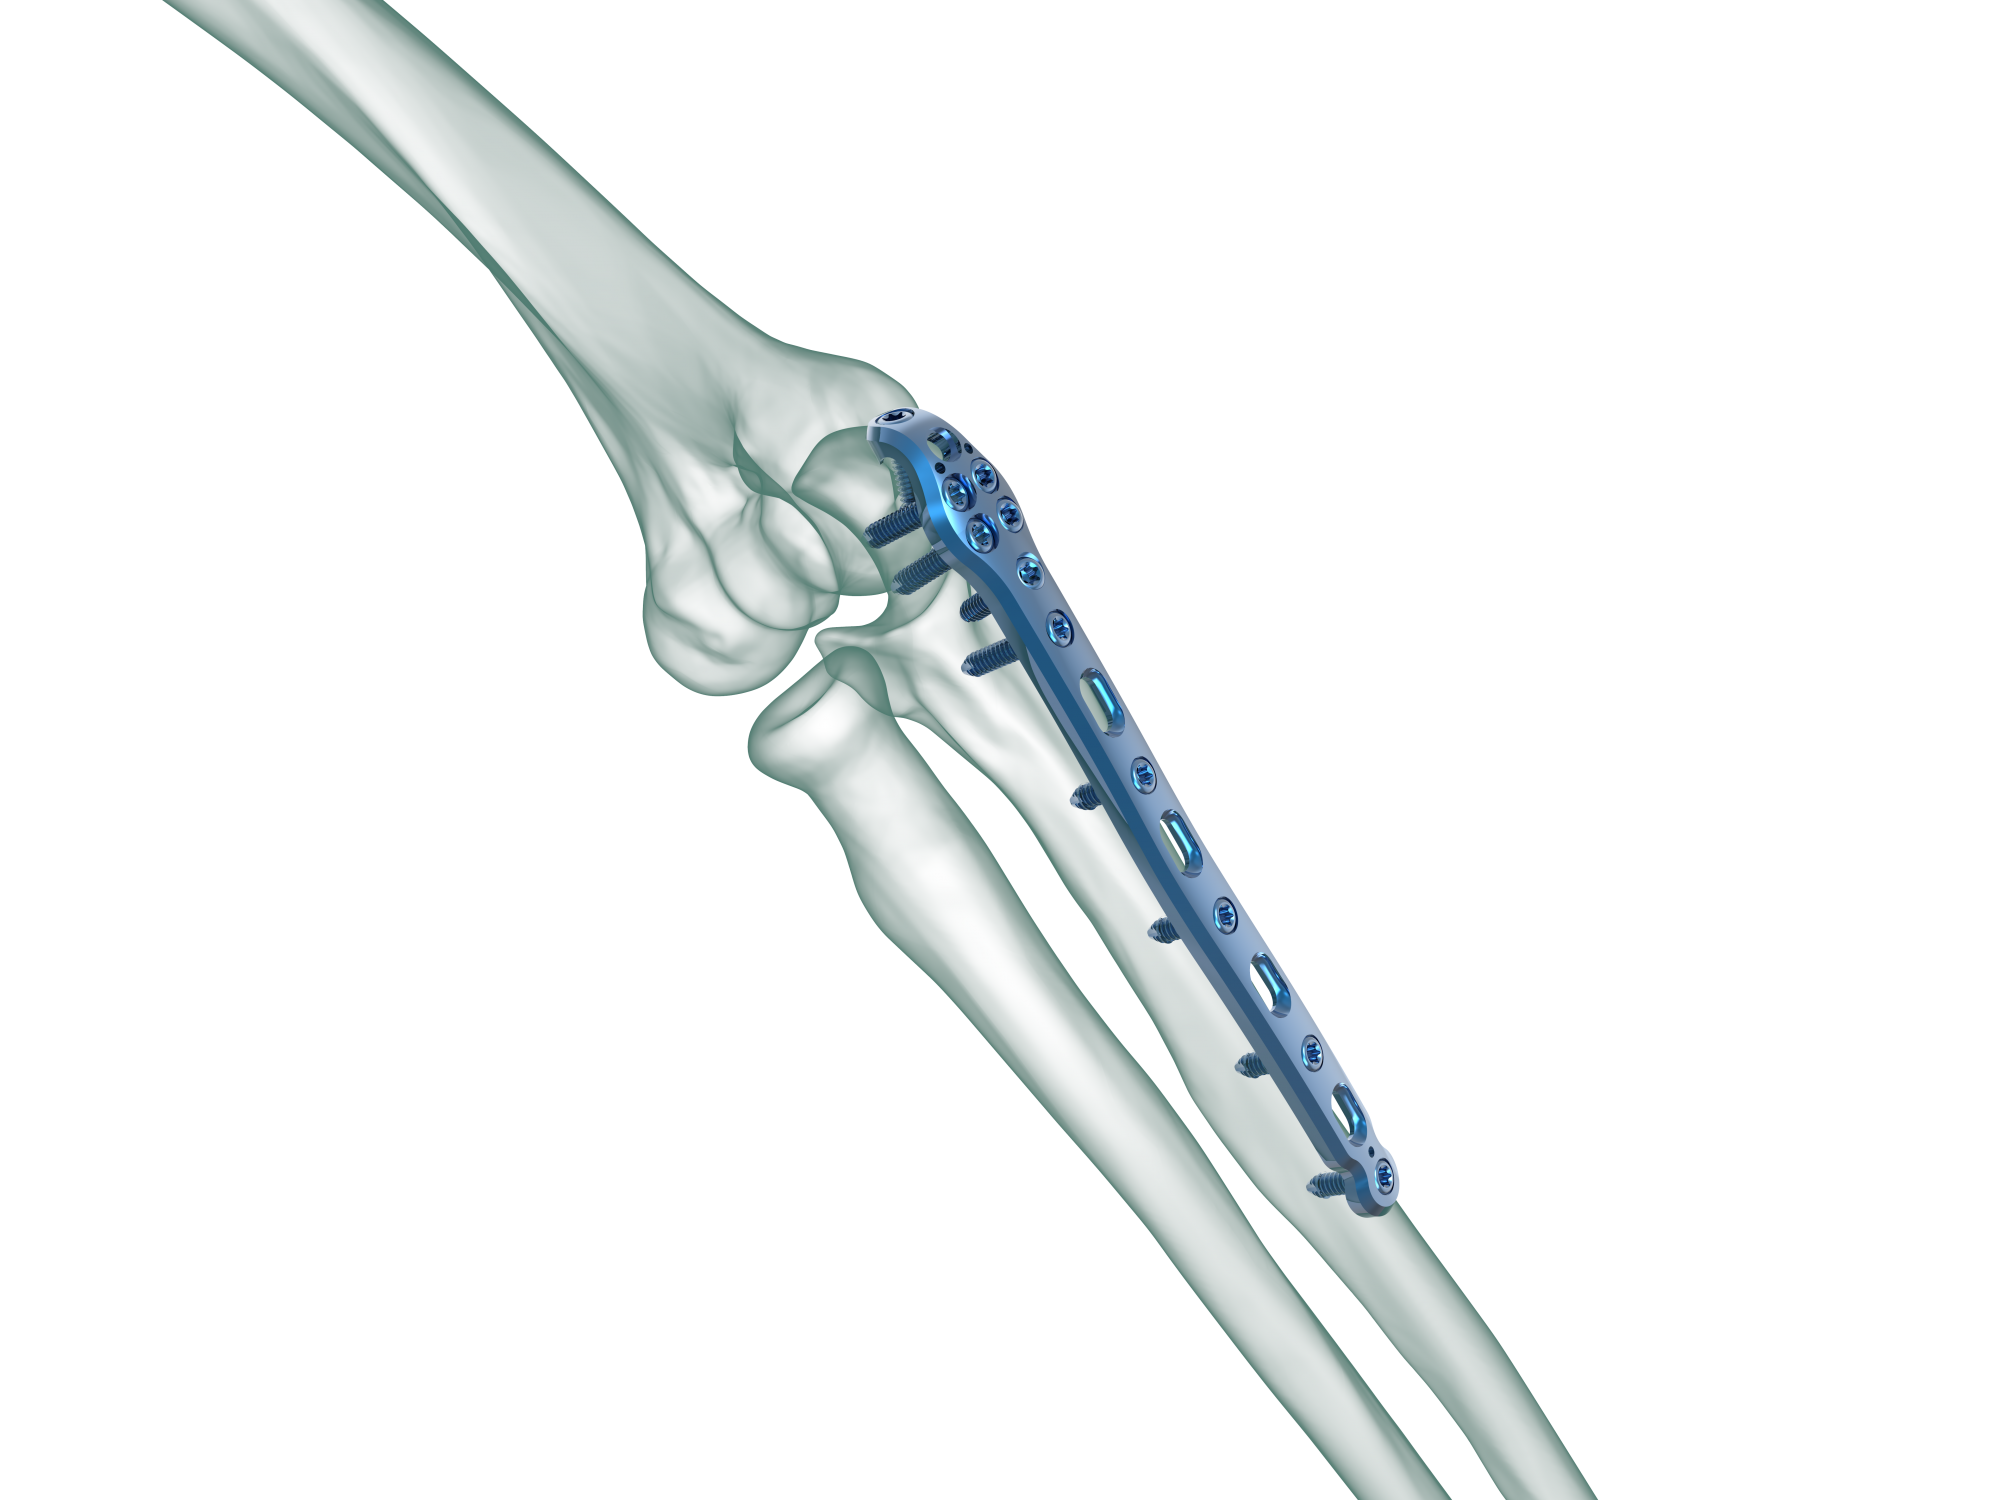

Low plate-and-screw profile and rounded plate edges minimize potential for tendon and soft tissue irritation.

TRUE LOCK Olecranon Anatomic Plates are precontoured for anatomic fit. No need to bend during teh surgery.

Elongated Combi hole in the neck and shaft facilitate plate adjustment and allow locking or compression options.

The combi-hole pro- vides flexibility of axial compression and locking capability throughout the length of the plate shaft.

Various screws target to help stabilize the coronoid, thereby helping to restore bony and ligamentous struc- tures, which are important for elbow-joint stability.

Long proximal extension and multiple screw options to secure small olecranon fragments to help neutralize the forces of the triceps muscle.

Kirschner wire holes accept Kirschner wires (up to 1.5 mm) to temporarily fix the plate to the bone, to temporarily reduce articular fragments, and to confirm the location of the plate, relative to the bone.